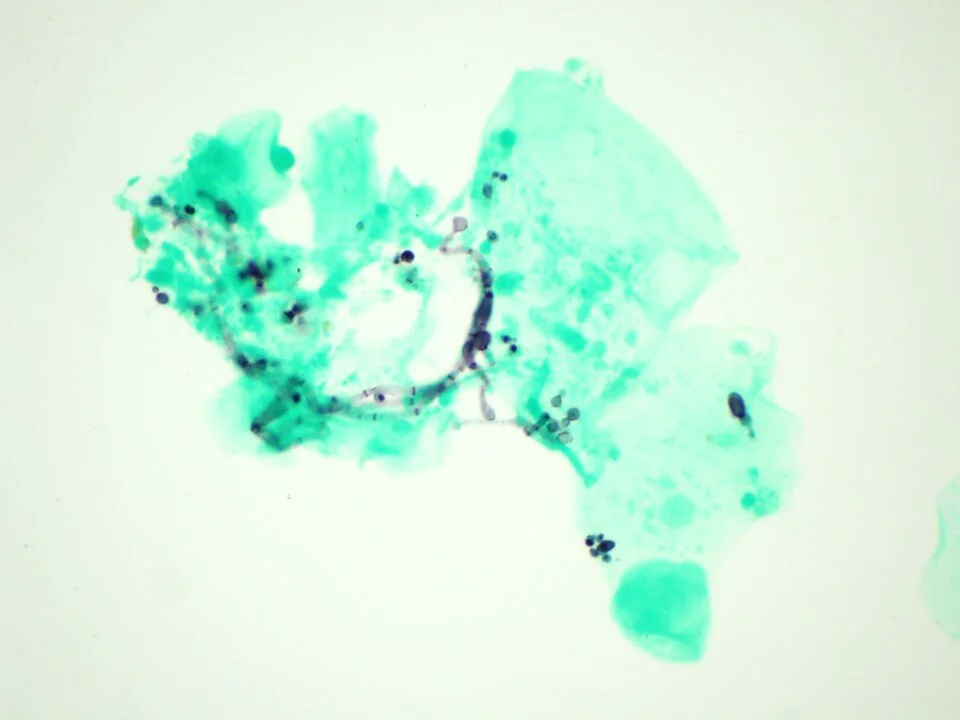

Pneumocystis jirovecii